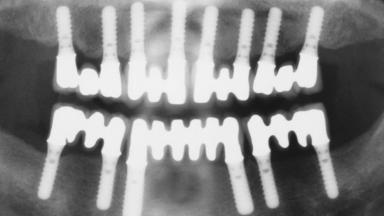

Immediate Loading of Eight Implants in the Maxilla and Six Implants in the Mandible and Final Restoration with Three-Unit and Four-Unit FDPs

# of Implants 14

Type of Implants One-Piece